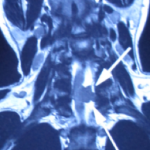

After detailed questioning, it is obvious that Mr. Lin’s problem has caused cauda equina syndrome. There may be a tumor in the spinal cord or a severe lumbar disc herniation compressing the spinal cord. Immediately arrange the patient to take a full spine MRI, and immediately after 2 hours after reading the scans, it turned out that the patient had a 1.6cm tumor at the 6/7 spinal canal position of the cervical spine and severely compressed the spinal cord. He was immediately referred to a neurosurgeon on the same day and arranged to be admitted to the hospital that night, and the cervical cord tumor was removed the next day by surgery. After the operation, the patient’s foot pain and numbness gradually improved.

Mr. Lin’s symptoms are generally considered to be sciatica. Although Lin’s foot pain and foot numbness are really similar to the symptoms of sciatica, but when the tumor is compressed against the spinal cord. This severe damage to the cord will lead to Mr. Lin’s severe fatigue in his feet and worsening pain at night, this indicated that the condition is not a normal condition of a sciatica. Although Mr. Lin’s tumor was on the cervical spine, he did not show symptoms of upper limb neuralgia or paralysis or weakness of the arms and hands. This kind of symptoms that a doctor can misdiagnosis as sciatica. Mr. Lin’s cervical spinal tumor is located outside of the spinal cord. When the tumor grows and large enough to compresses on the spinal cord, the following symptoms will appear: